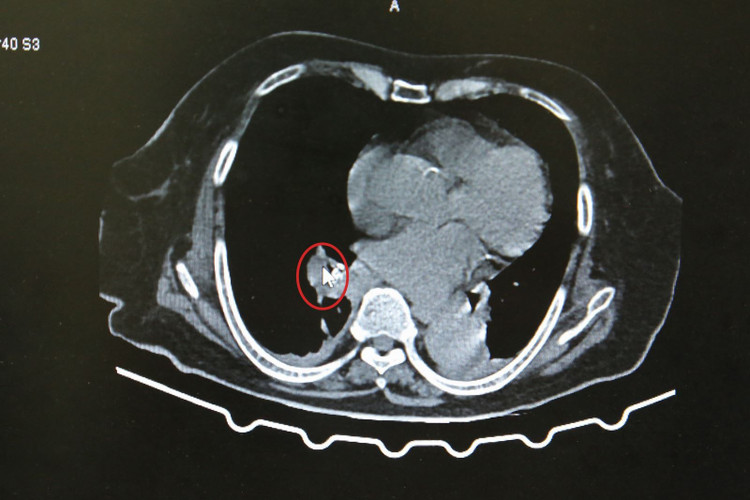

Bệnh nhân là N.T.L (90 tuổi) ở phường Cao Xanh, tỉnh Quảng Ninh, đang điều trị viêm mô bào cổ trái và gãy mấu chuyển xương đùi trái tại Bệnh viện Đa khoa tỉnh. Trong quá trình thăm khám, chụp cắt lớp vi tính lồng ngực, các bác sĩ phát hiện hình ảnh tổn thương đông đặc nhu mô dạng xẹp phổi phân thùy dưới phổi phải, nghi ngờ do có dị vật nằm trong phế quản tương ứng vị trí xẹp phổi.

Hình ảnh nghi ngờ dị vật trong phế quản qua phim chụp cắt lớp vi tính lồng ngực - Ảnh BVCC